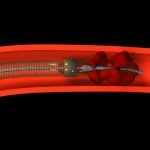

Filtre yerleştirilmesi: Bazen tüm çabalara karşın akciğer embolisini engellemek mümkün olmaz. Tedavi başarısız ise, tedavi başlanamamış yada yarıda kesilmiş ise akciğer emboli riskini azaltmak için toplar damar içine pıhtıları engelleyen bir filtre yerleştirilmesi gerekebilir. Vena kava filtresi

yönteminde kasıktan ya da boyundan kateterlerle en büyük toplar damar olan karındaki vena kava inferiyora yerleştirilir.